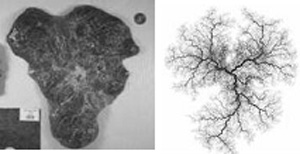

deformed placental shape and model

Deformed placental shape (left) and the model (right).

Salafia and Yampolsky also studied the relation of placental mass to fetal metabolism, and a resulting scaling relation between fetal mass and placental mass. As predicted by the model, a pathological placental shape is associated with a reduced metabolic efficiency, which results in a lower fetal birth weight. These findings are published in a recent article in Placenta, [Placenta, 29 (2008), 790-797] and several other papers are currently under review.